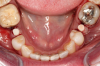

Fig 1. Preoperative surgery.

Figure 1

Fig 2. Extractions and immediate placement.

Figure 2

Figure 1 and Figure 2 depict the preoperative image and subsequent removal of three posterior teeth, immediate placement of zirconia-oxide ceramic dental implants, and soft-tissue augmentation with platelet-rich fibrin (PRF) to enhance the soft-tissue architecture surrounding the ceramic implants. The teeth were removed atraumatically and without suture placement. Because the implants were one-piece in stature (the abutment was incorporated into the implant), the recommendation was to splint the multiple units to minimize the lateral forces from mastication, swallowing, and tongue movement.